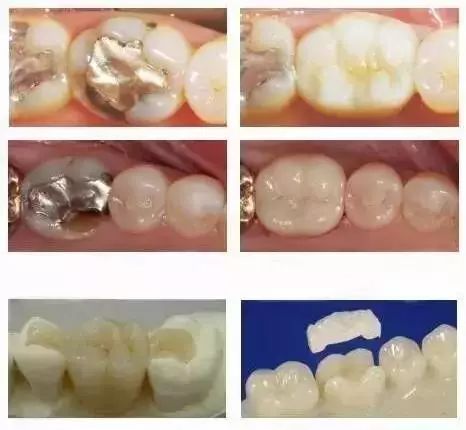

嵌体和传统的补牙不同之处在于:普通充填术做充填治疗时一般用银汞合金、光固化复合树脂等,不需要技工配合,医生可以独立完成,所需时间短、费用低。而嵌体是在口外石膏模型上由专门的牙科技师制作出来的,然后再由临床医生将其戴入患者口内,最终粘固形成的,价格也较高。

普通合金嵌体:价格便宜,延展性较差。

瓷嵌体:颜色逼真度高,但对医生的制作要求高,使用不当有碎裂可能,较金属嵌体导热性低,深龋不易刺激牙髓组织。

超瓷嵌体:颜色较金属嵌体逼真,接近于牙齿颜色,超硬树脂材料。抗折强度和耐磨性不如金属嵌体。

黄金嵌体:延展性最好,长期使用密合度高,不易发生继发龋(再次蛀牙),生物相容性也较好,长期使用对人体无任何副作用。

金属嵌体与瓷嵌体的修复对比